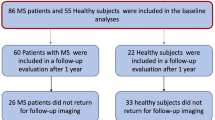

Mean kurtosis (MK), axial kurtosis (AK), radial kurtosis (RK), kurtosis fractional anisotropy (KFA), and the mean relative quantitative susceptibility mapping (mrQSM) values in the U-fiber region were compared between 49 pwRRMS and 48 healthy controls (HCs). The U-fiber were divided into upper and deeper groups based on the location. The whole brain volume, gray and white matter volume, and cortical thickness were obtained. The correlations between the mrQSM values, DKI-derived metrics in the U-fiber region and clinical scale scores, brain morphologic parameters were further investigated.